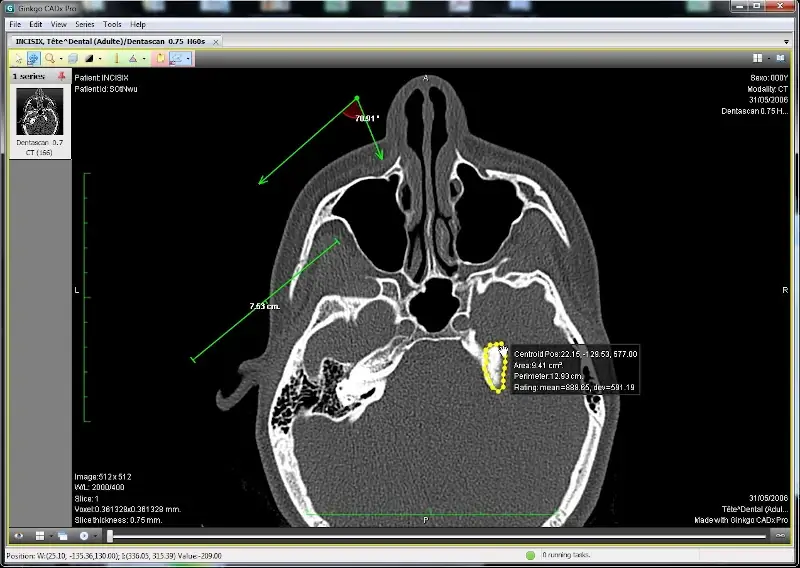

13. Ginkgo CADx

Ginkgo CADx is an advanced open-source application tailored for medical imaging provides a range of tools for visualization, analysis, and interpretation of various medical images.

Whether it’s DICOM, X-rays, CT scans, or MRIs, this software ensures seamless viewing and management. Beyond mere visualization, Ginkgo CADx supports a variety of image enhancement and annotation tools, aiding professionals in accurate diagnostics.